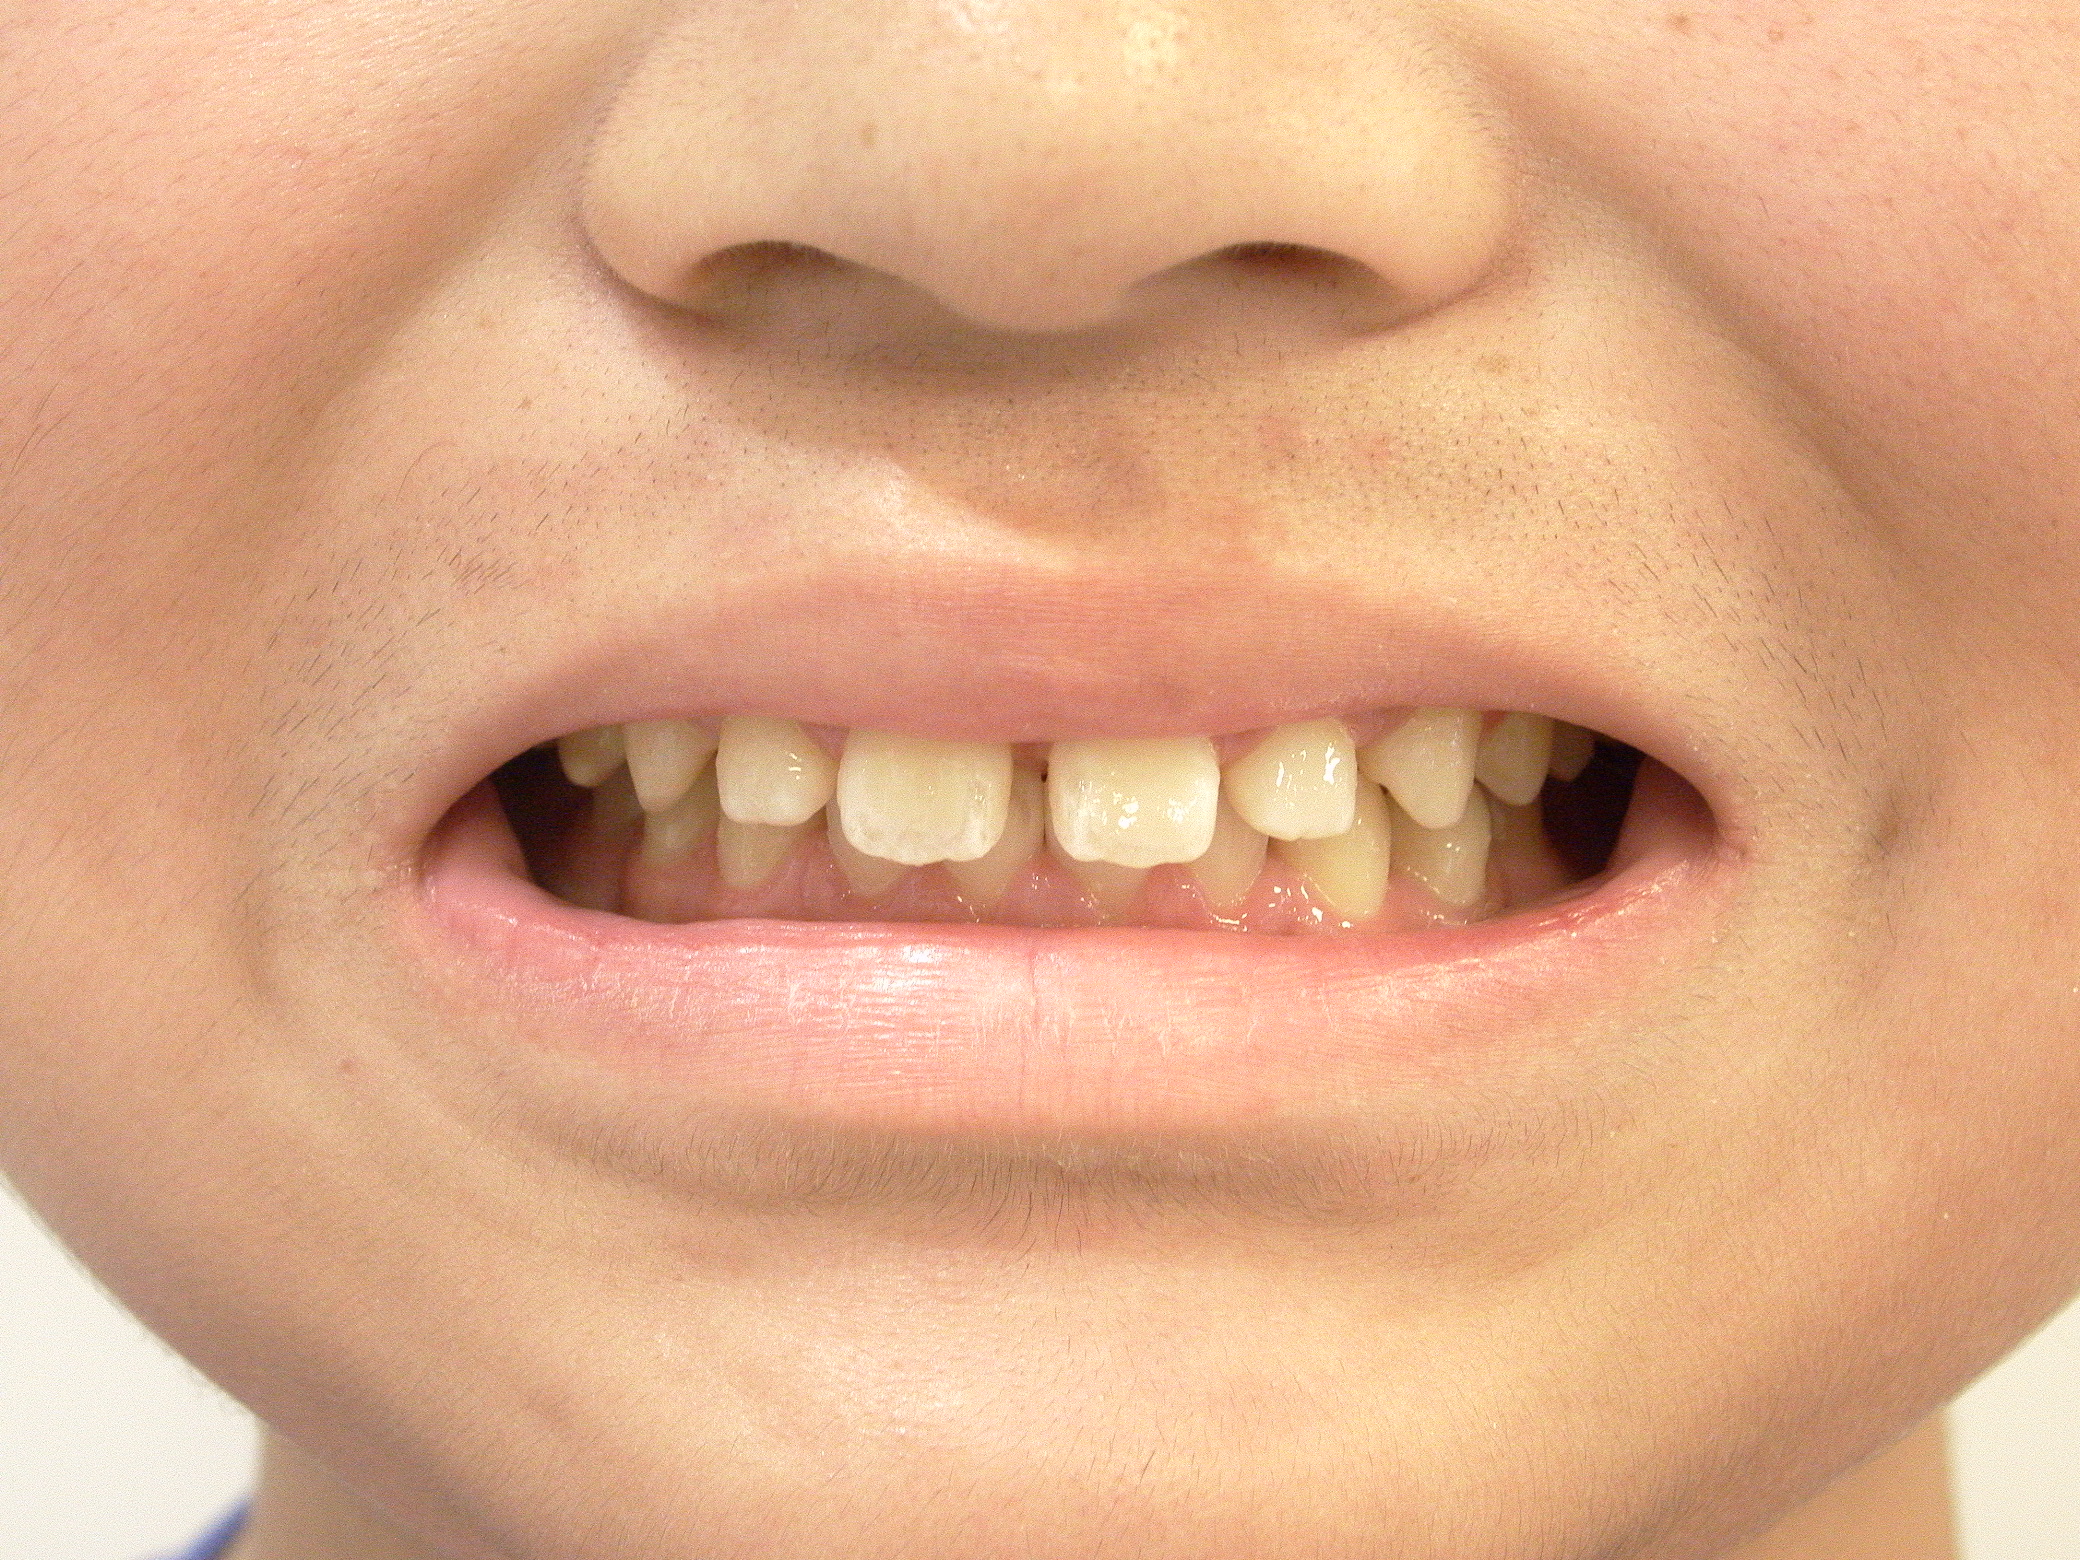

叢生(マウスピース矯正)

7歳 女性

カスタムメイド型マウスピース矯正装置(インビザライン)による歯列弓拡大、叢生の改善

カスタムメイド型マウスピース矯正装置(インビザライン)

605,000円(税込)

約1年

マウスピース矯正装置(インビザライン)にて効率よく歯列弓拡大と叢生を改善しています。

ホーレータイプリテーナー(保定装置)を使いながら大人の歯が生えそろうまで経過観察中です。